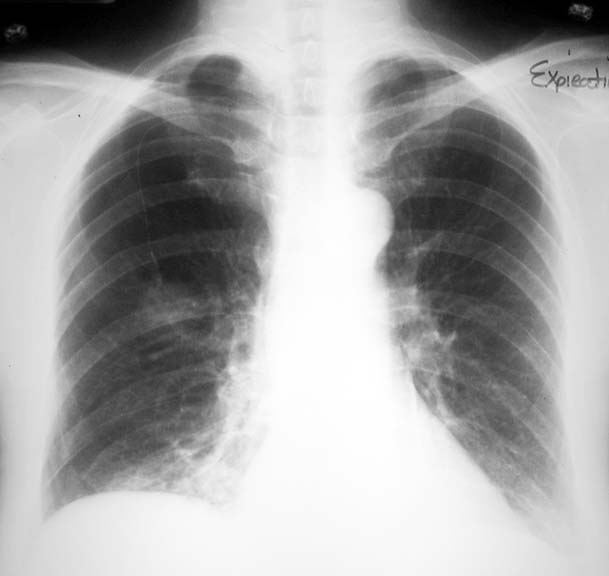

Note the bulbous end of indwelling catheter is projecting at various sites of the chest and can be mistaken for a lung lesion.